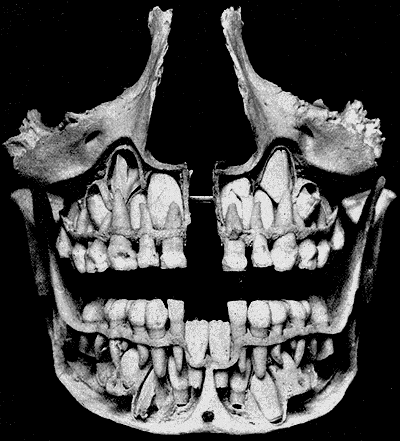

Vývoj postupuje za pomoci amelogeneze (tvorba skloviny) a dentinogeneze (tvorba zuboviny) specializovanými buňkami od korunky zubu dolů ke kořeni, který se vyvíjí až do 3 let věku. Resorpce (zpětné vstřebávání) začíná hned od 4,5 let a začíná na vrcholu kořene, je způsobena tlakem vyvíjejícího se trvalého zubu pod ním. Tím, jak postupně první zuby resorbují, vypadnou, protože nemají již kořen, který by je držel v lůžku. Samotný vývoj trvalého chrupu začíná od 6. měsíce po narození.  Zuby se zakládají a jejich následný vývoj probíhá v tělech čelistí (viz obrázek odkrytých vnitřních částí čelistí dítěte).